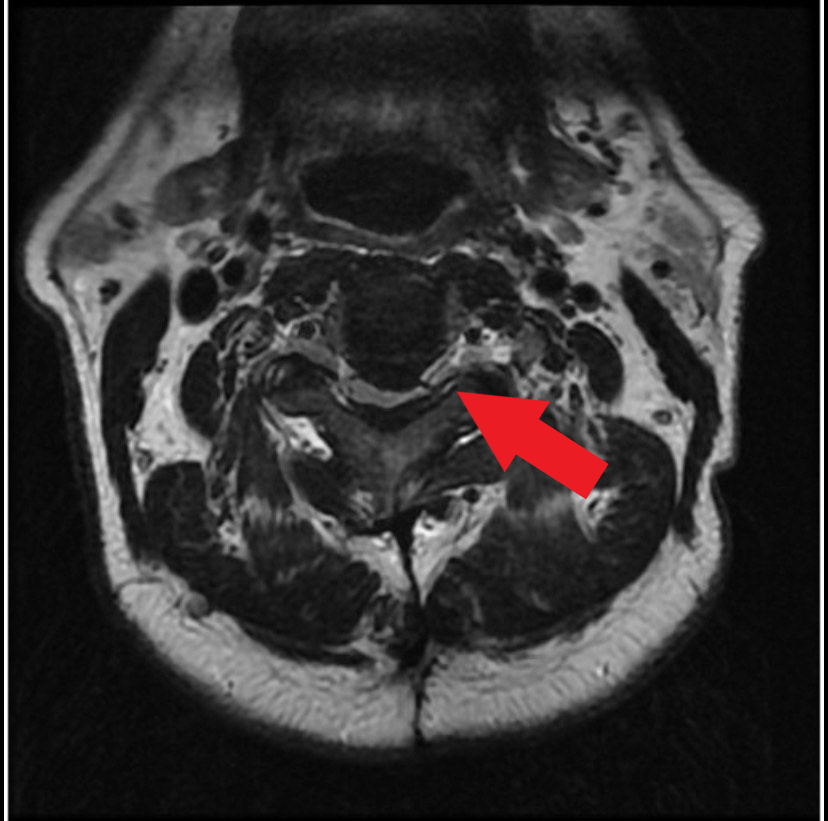

圖:經MRI檢查發現病人的第二、三節頸椎後縱韌帶骨化非常嚴重,受壓迫的神經幾乎扁成一條線。

圖:術前檢查,高位頸椎後縱韌帶骨化,嚴重擠壓脊髓神經。